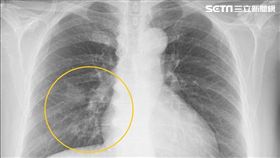

8成確診已末期!1飲食習慣成癌王元凶

原要開刀治療痔瘡 婦人竟診斷出肺癌

肺癌不易早期發現,彰化67歲詹姓婦人卻相對好運!她治...